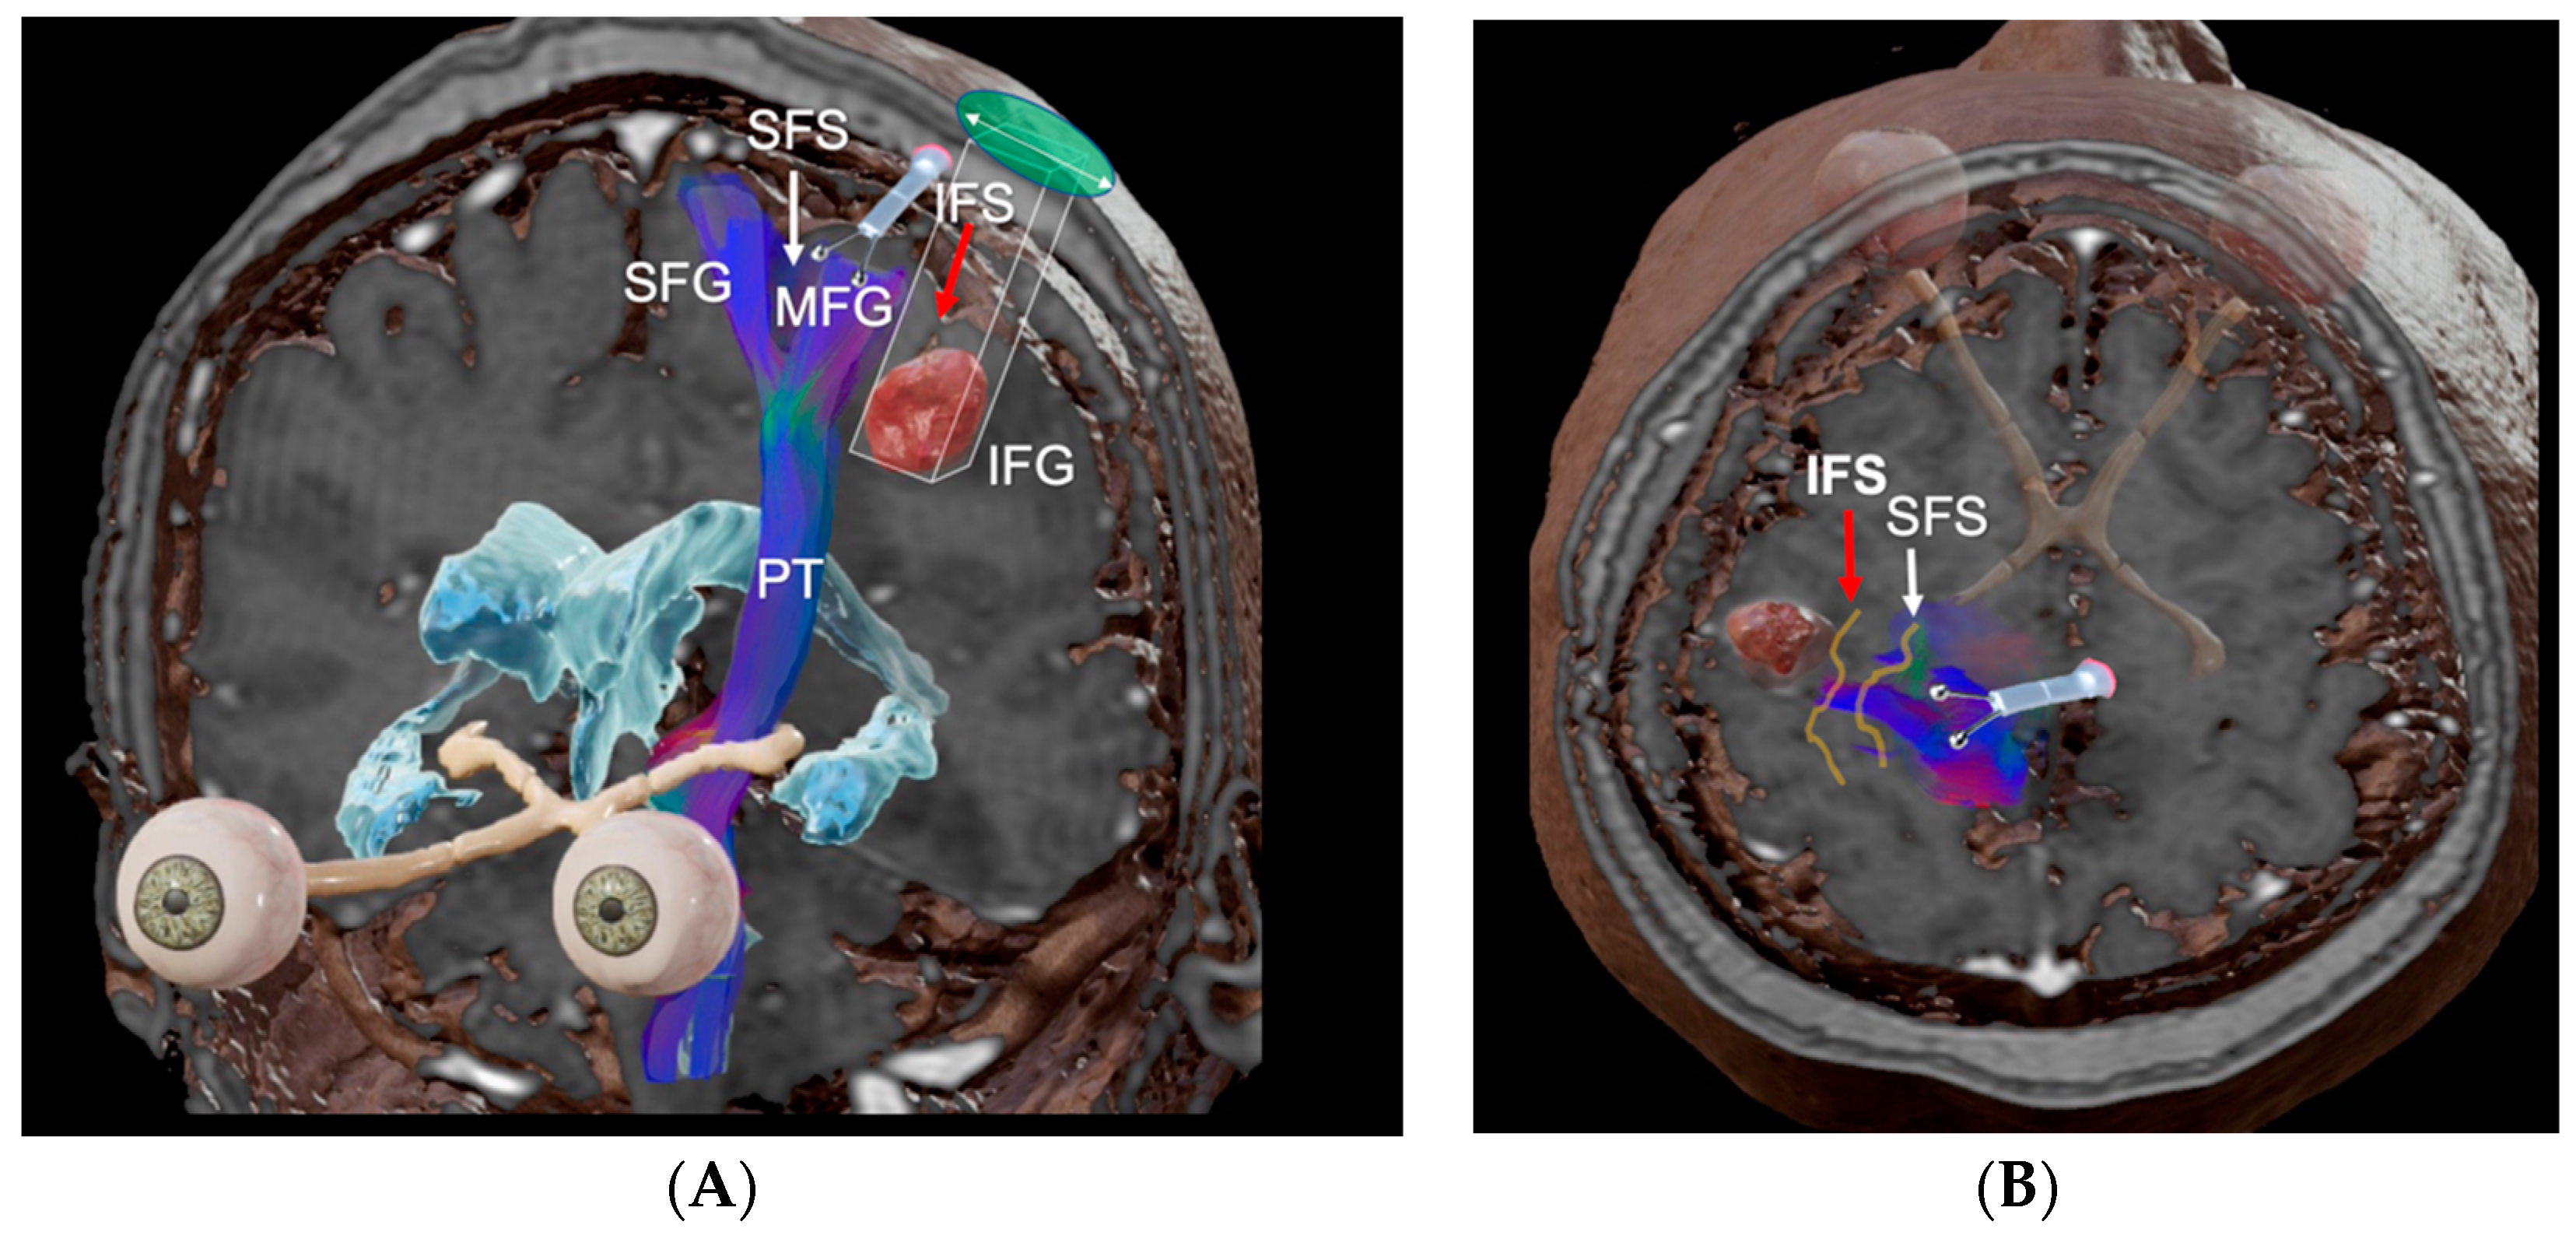

2.5. Eight Step Strategy for PTA Design

4.3. Surgical Nuances